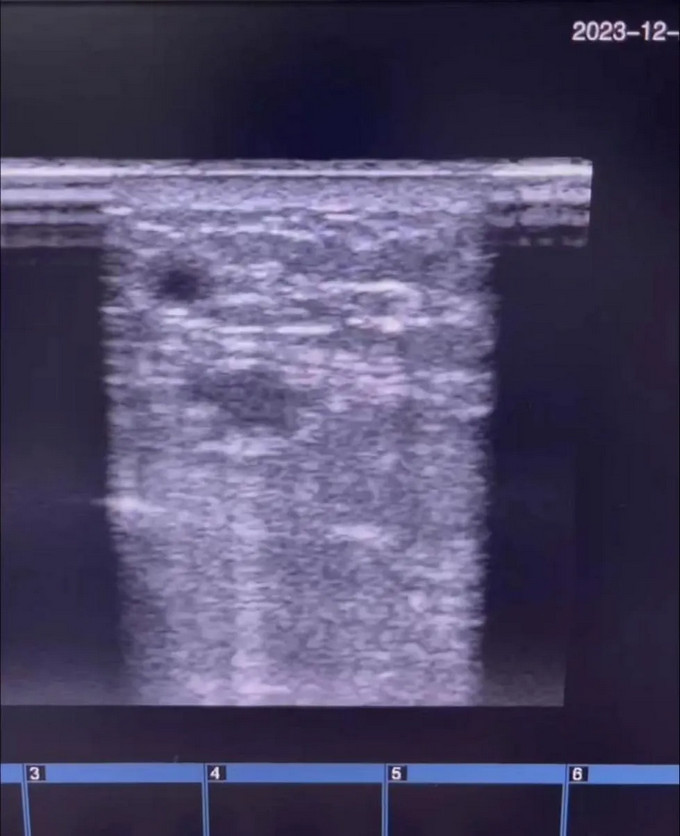

手术由肾病科张主任、李医师完成,历时1小时,手术中张主任耐心置入导丝,并在导丝引导下置入扩张球囊,经过多次扩张,确认狭窄消失,血流通畅。术后超声复查最窄血管内径扩大至4.0毫米,内瘘震颤明显比术前强烈,而且手术次日便能够穿刺内瘘透析,血流量又达到了230ml/min,保障了血液透析的充分性。

手术后